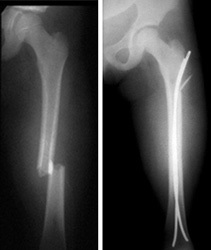

Fractured Femur Before & after surgery